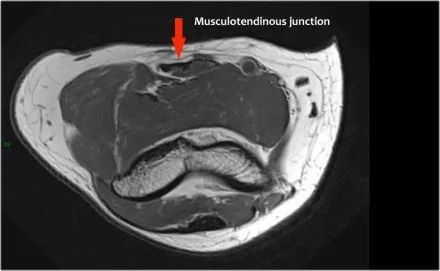

在矢状面上,比较肱肌腱(黄色箭头)和二头肌腱(红色箭头)时,注意肱肌几乎都是肌肉。它只有一个非常短的肌腱远端。